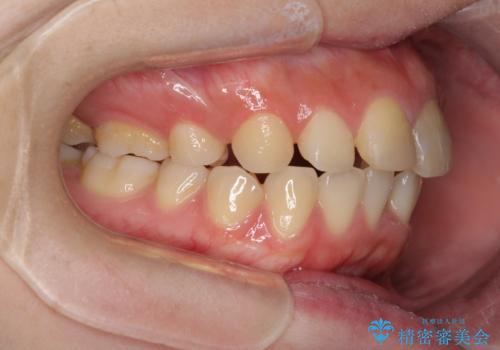

抜歯矯正の後戻り インビザラインによるオープンバイトの再矯正

- 以前矯正治療をされていましたが、後戻りが起きたことを気にして来院された患者様です。

上下前歯のオープンバイトを改善するため、インビザラインにて治療を行うこととしました。